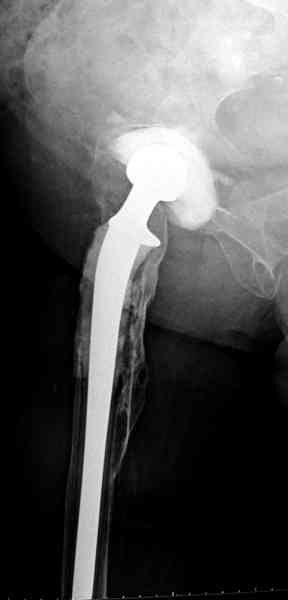

Приглашенный хирург установил ревизионный вариант бедренного компонента без замены ацетабулярного компонента, что осложнилось нагноением и свищами на уровне сустава и средней трети бедра. После двухгодичного безуспешного лечения перевязками и антибиотиками больная обратилась к нам на консультацию.

Для спейсера в бедро использовал старый длинный бедренний компонент меньшего диаметра, облепленный со всех сторон цементом с антибиотиком.

№3-6 снимки с осложнением